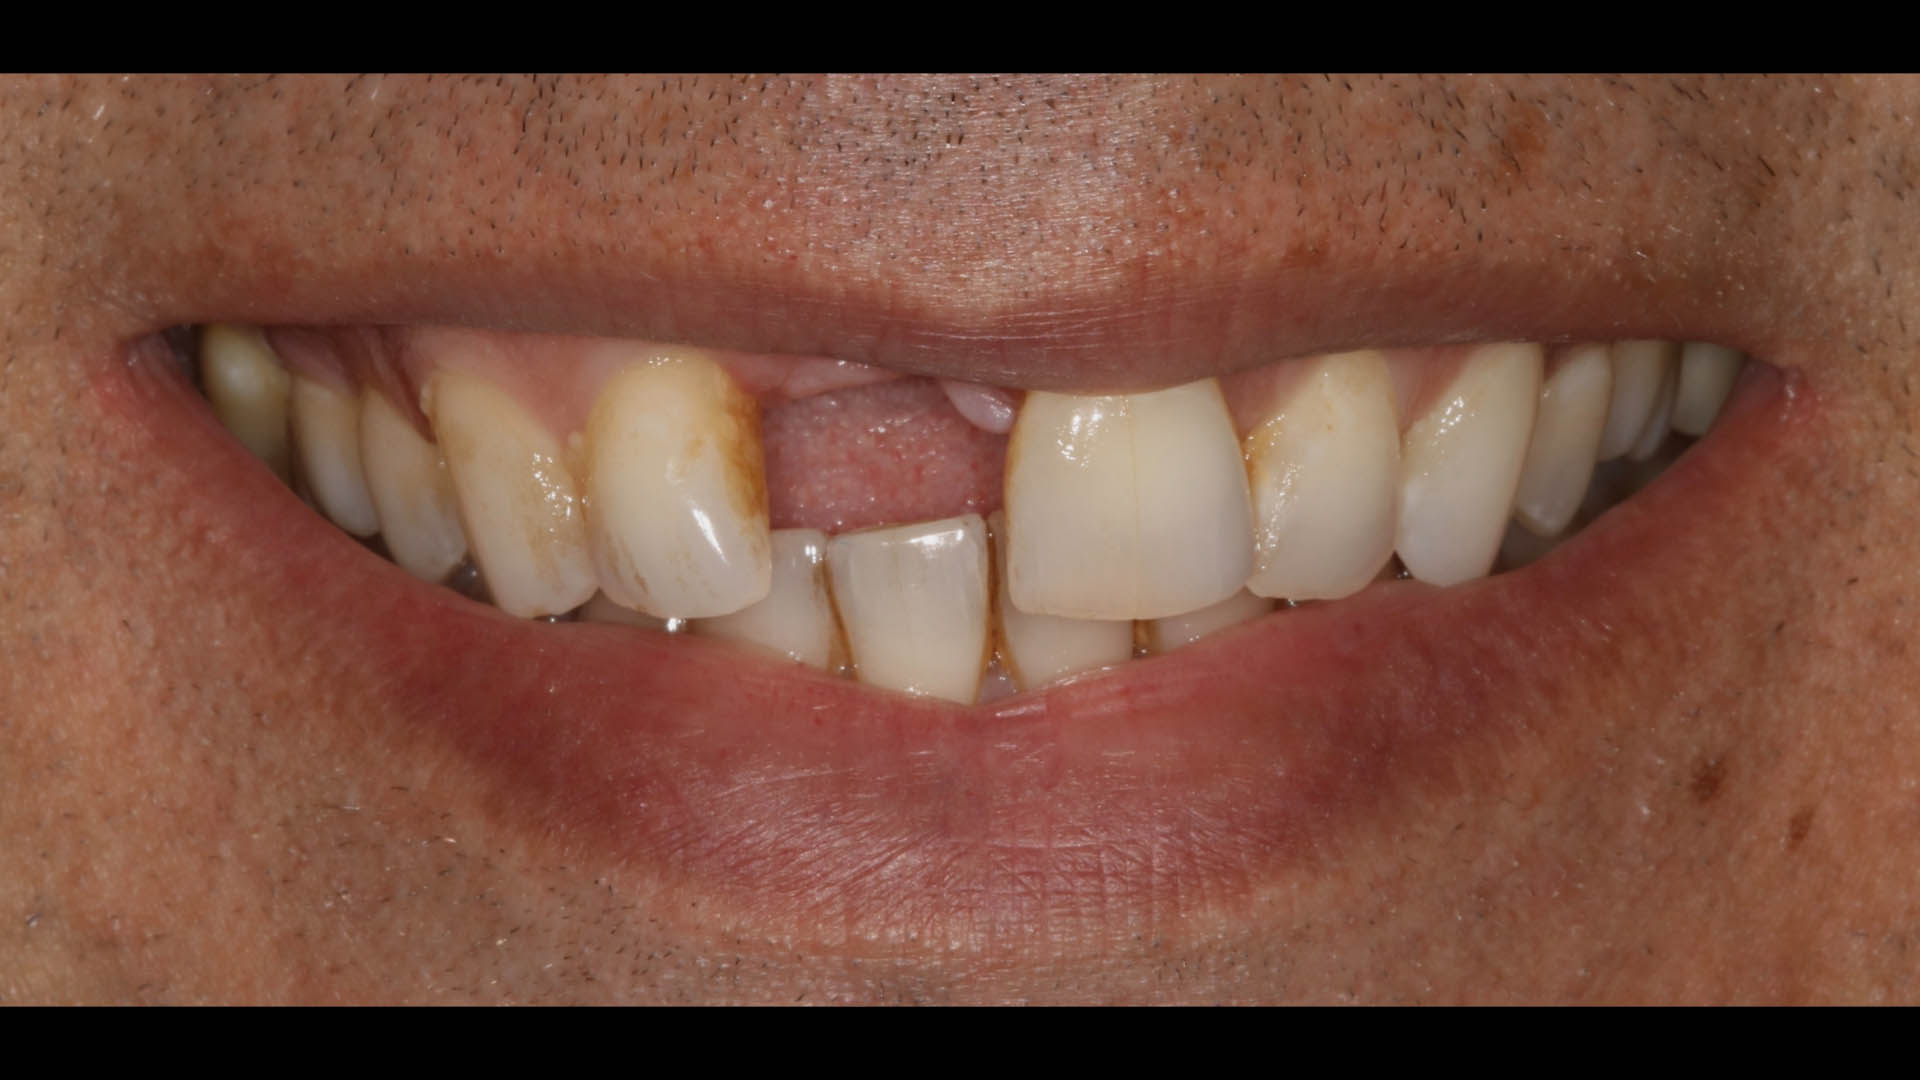

Take a glimpse into the magic of Coral Gables Dentistry through our before and after pictures. See firsthand the incredible smile makeover transformations that have brought confidence and joy to our patients.